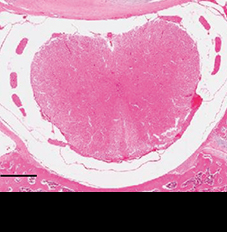

척추관 및 척수 형태 회복

척추관협착증을 유도한 쥐는 척추관이 좁아져 척수의 모양이 망가집니다.

여기에 신바로2를 투여하자 척추관과 척수의 형태가 정상에 가깝게 회복됐습니다.

정상 쥐

척추관협착증 유도 쥐

신바로2 약침 투여 쥐